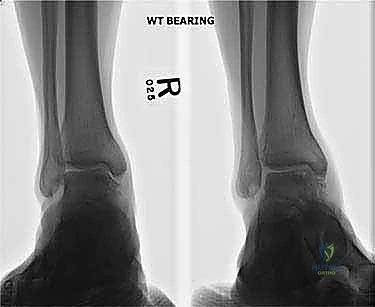

- التصوير بالأشعة السينية (X-rays): الخطوة الأولى لاستبعاد الكسور الكبيرة وتقييم المحاذاة العامة للعظام. قد تظهر الأشعة السينية الآفات الكبيرة، لكنها غالباً ما تفشل في إظهار التلف الغضروفي المبكر.

- التصوير بالرنين المغناطيسي (MRI): هو "المعيار الذهبي" لتشخيص آفات الكاحل. يوضح الرنين المغناطيسي بدقة متناهية حالة الغضروف، حجم التكيسات العظمية، ومقدار التورم داخل العظم (Bone marrow edema). من خلال صور الرنين، يحدد الدكتور هطيف أبعاد الآفة (الطول، العرض، العمق) بدقة المليمتر.

- التصوير المقطعي المحوسب (CT Scan): ضروري جداً للآفات الكبيرة. يوفر الـ CT صورة ثلاثية الأبعاد للعظم، مما يساعد الجراح في التخطيط الدقيق لعملية قطع العظم وحجم الطعم المطلوب زراعته.